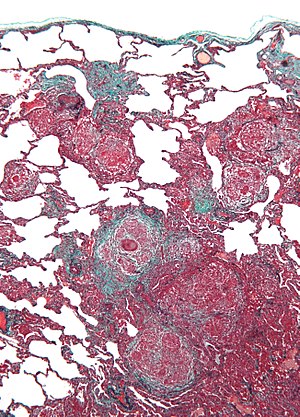

Hypersensitivity pneumonitis. Trichrome stain. | |

| LM | centrilobular prominence of lesions, granulomata, chronic interstitial inflammation consisting primarily of lymphocytes, interstitial fibrosis, air space involvement (alveolitis) |

- Lesions have centrilobular prominence - important feature. [6]

- Allergens enter lung through airway which has a centrilobular location.

- Granulomata (not typically seen in UIP) - important feature.[6]

- Chronic interstitial inflammation consisting primarily of lymphocytes.

- Interstitial fibrosis.

- Air space involvement (alveolitis).